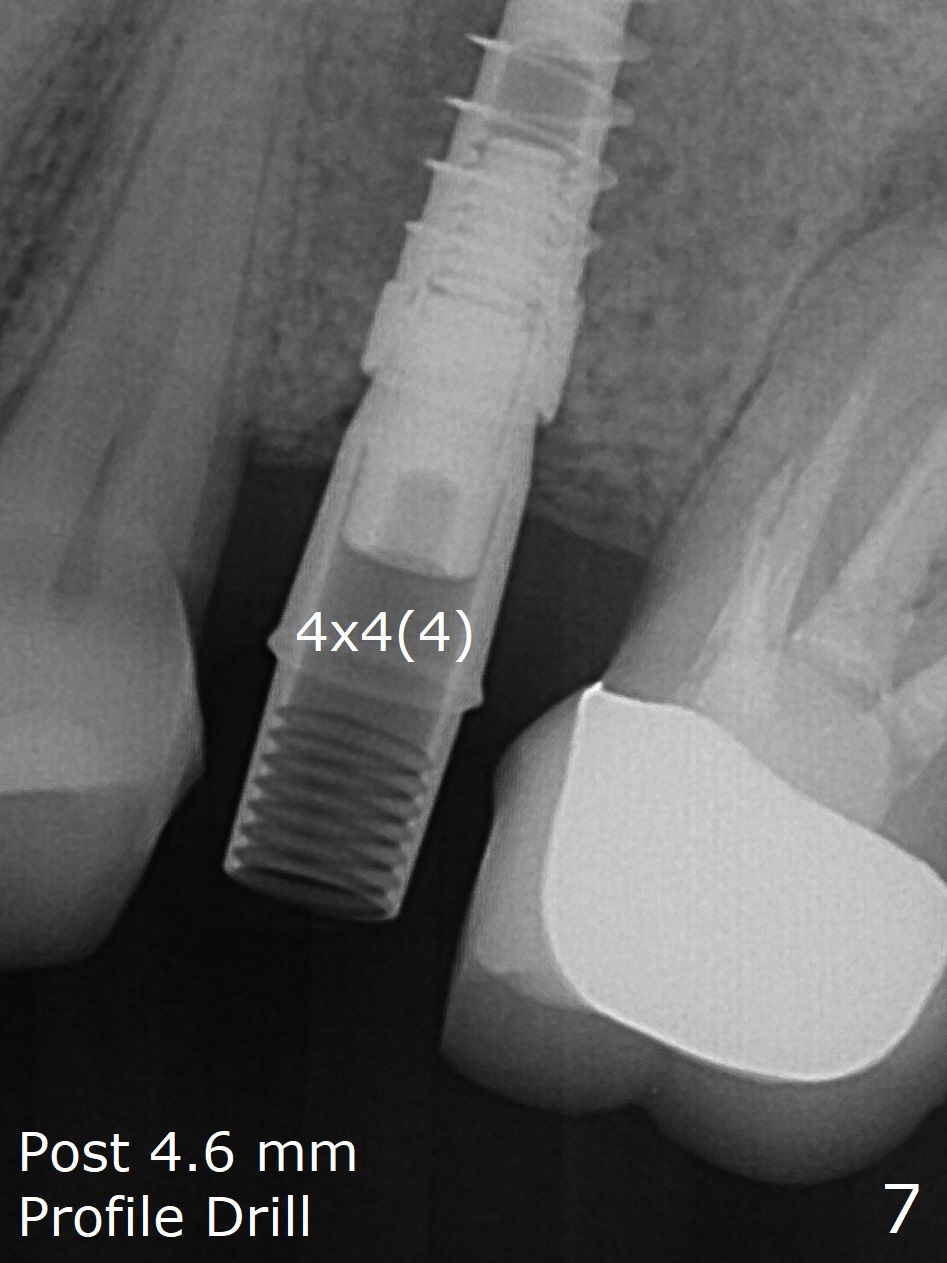

The palatal gingival margin of the tooth #15 with vertical root fracture is low, consistent with the low palatal plate after extraction (Fig.1 >). With IS guide, a 5x11 mm IBS implant is placed in the septum with >5 mm the palatal gap. After underprep in depth, a 3.5x9 mm achieves primary stability (Fig.2,3). The palatal defect is repaired with allograft (*) and 2 pieces of PRF membrane. The palatal soft tissue defect appears to have been repaired 6 months postop (Fig.4,5). When a narrower abutment with longer cuff is placed at #15 (6x4(4) mm in Fig.6, as compared to 6.5x4(3) mm one in Fig.2), there is no gap between the implant and abutment. In contrast there is one at #13 (Fig.6 <) when a 4x4(4) mm abutment is seated following removal of a 4x4 mm healing abutment. After use of a 4.6 mm profile drill, the gap disappears (Fig.7). Impression is taken.